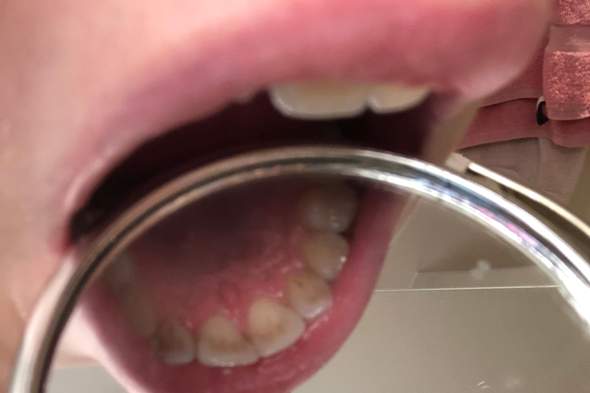

Etwa einer von vier Jugendlichen hat weiße Flecken auf den Zähnen Diese sind an den Schneidezähnen besonders auffällig, denn dort heben sich hellere Flecken sehr deutlich von der umliegenden Zahnsubstanz ab Dennoch können weiße Flecken auch im Bereich der Eck oder Backenzähne auftreten und sowohl einzelne Zähne als auch komplette Zahnreihen betreffen. Wie Sie weiße Flecken auf den Zähnen schonend, einfach und schnell entfernen lassen Nicht nur gelbe Verfärbungen der Zähne, sondern auch weiße Flecken auf den Schneidezähnen können einem das Lächeln schwer machen Diese sogenannten White spots lassen die Zähne unebenmäßig und unschön erscheinen. White Spot Weiße Flecken auf den Zähnen Credit Published with the permission of DMG DentalMaterial Gesellschaft mbH White Spots sind oft der Beginn kariöser Zähne Der Verlust gesunder Zahnsubstanz durch Karies ist bis heute ein häufig auftretendes Problem Doch dank moderner Wissenschaft kann Karies jetzt immer früher erkannt werden.

Das könnte Sie auch interessieren Weiße Zähne Verfärbungen entfernen Weisheitszahn ist durch Karies abgebrochen Wenn durch großflächige Zerstörung durch Kariesaktivität die Zahnhartsubstanz soweit geschwächt wird, dass die Zahnkrone instabil wird, kann es zum Abbrechen von Zahnteilen kommen. Manch einer mag erschrecken, wenn er beim morgendlichen Blick in den Spiegel auf einmal weiße Flecken auf seinen Zähnen entdeckt Besonders unangenehm ist es, wenn sich diese auf den Schneidezähnen befinden und somit direkt ins Auge stechen Aber ist das normal?. Weiße Flecken auf den Zähnen Wie entfernt man die White Spots?.

Weiße Flecken auf den Zähnen Nicht nur Ihre Zahnfarbe, sondern auch die Form und Struktur können Ihr Selbstbewusstsein erhöhen oder zu Ihrem Unwohlsein in Gesellschaft beitragen Fleckige Zähne wirken nicht nur unschön, sondern lassen Ihre Mitmenschen häufig auf eine schlechte Zahnpflege und Mundhygiene schließen. Im frühen Stadium der Erkrankung verläuft Karies ohne Beschwerden oder Schmerzen Erste Anzeichen stellen sich als weiße Flecken am Zahn dar, die dadurch zustande kommen, dass die Bakterien Mineralstoffe aus dem Zahnschmelz lösen Bei bereits bestehenden Defekten des Zahnschmelzes verfärbt sich die betroffene Stelle gelb oder braun. Normalerweise weiße Flecken auf Zähnen sind kosmetisches Problem, aber manchmal können sie zu Karies führen zu und somit wird es wesentlich, weiße Flecken auf den Zähnen zu entfernen Diese unnatürliche helle Flecken auf den Zähnen kann oder auch nicht zeigen Verfall der Zähne abhängig von der zugrunde liegenden Ursache.